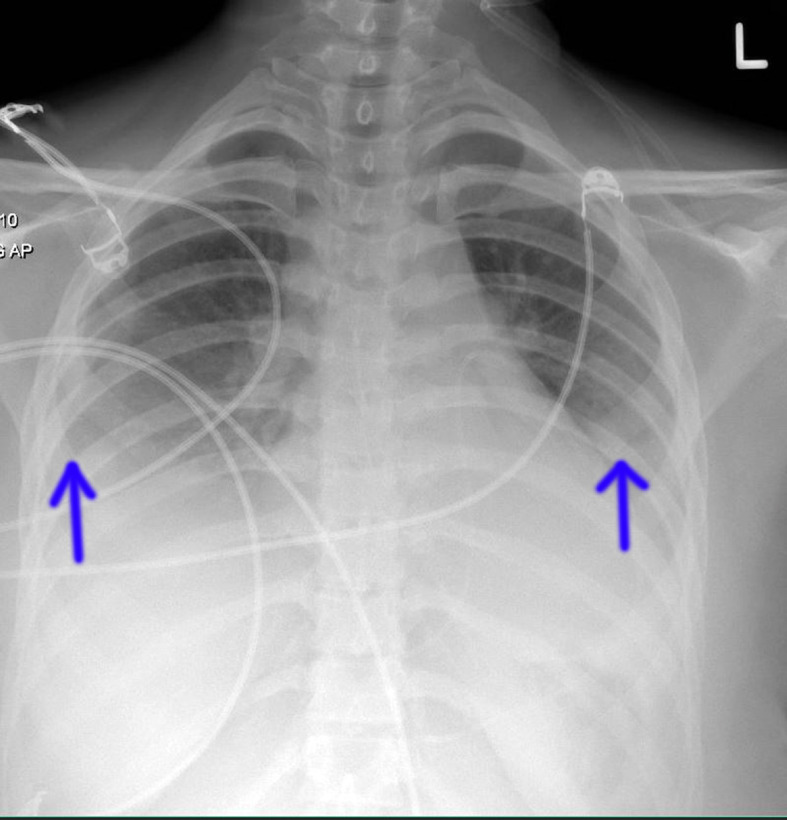

Case summary: We report the case of a 22-year-old immunocompetent female who presented to the emergency department with acute shortness of breath, fatigue, and dizziness due to symptoms suggestive of an influenza-like illness. Laboratory and imaging findings revealed a large circumferential pericardial effusion suggestive of cardiac tamponade. Subsequent investigations confirmed influenza B infection. The patient was managed with pericardiocentesis, oseltamivir, nonsteroidal anti-inflammatory drugs, colchicine, and supportive care, resulting in complete recovery. This case highlights the significance of considering influenza as a potential cause of acute cardiac complications and the importance of early diagnostic and therapeutic interventions to prevent morbidity and mortality.